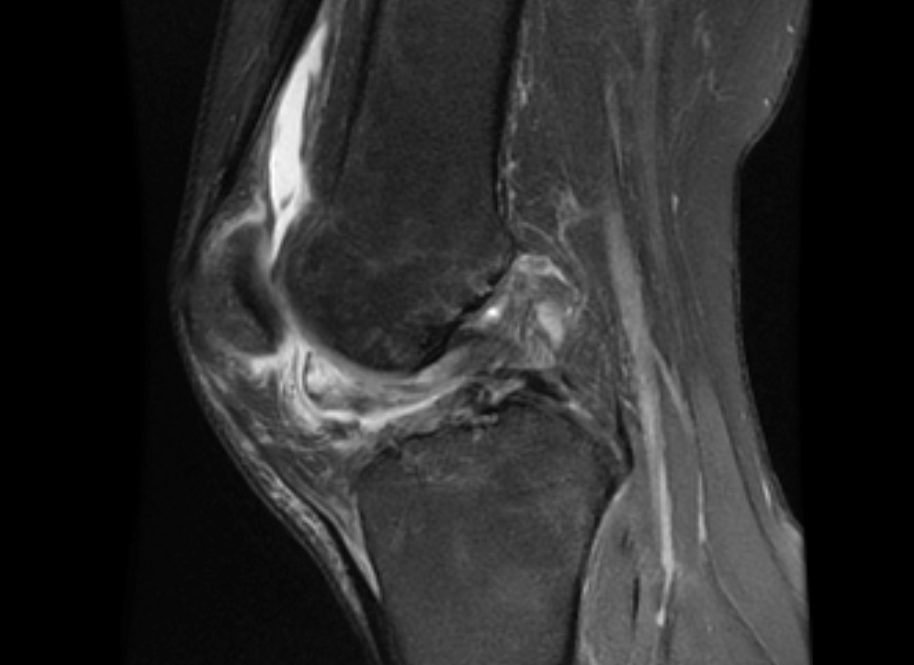

Post-Operative MRI Showing Anatomic Healed Avulsion Fracture in Sagittal View